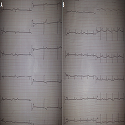

An unusual manifestation of hyperkalemia

Ahmed Belkouch, Lahcen Belyamani

PAMJ. 2014; 19: 251. Published 07 November 2014